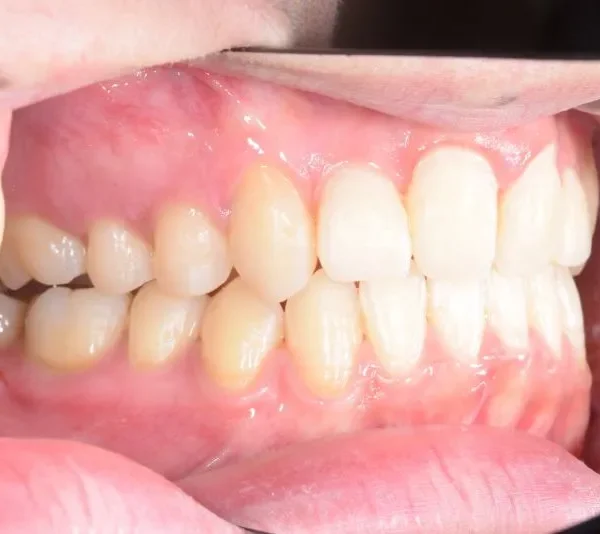

【大人の矯正】叢生・八重歯・交叉咬合・非抜歯症例・19歳女性【R.T様】

初診時年齢 19~29歳 (女性) 主訴 ガタガタ・交叉咬合が気になる

診断名 叢生・交叉咬合 装置名

ガタガタ・八重歯を主訴に来院された患者様です。

頬杖をする癖がおありでした。

初診